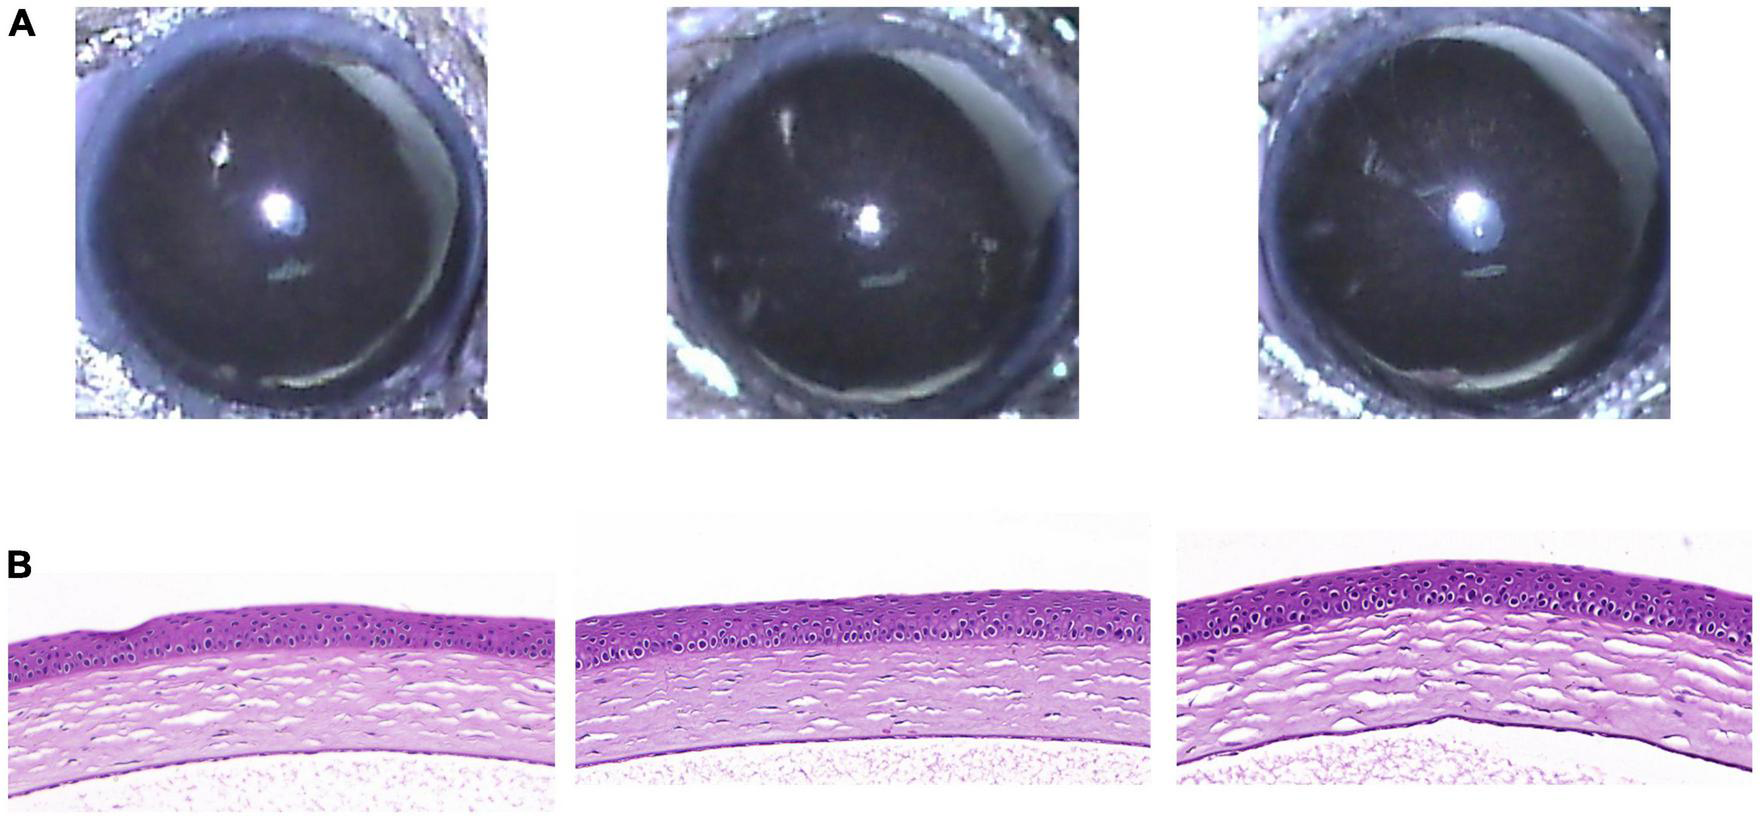

Five weeks after eye drop application, the RCI group showed no significant abnormal changes on the ocular surface, such as corneal epithelial defects or stromal opacity (Figure 4A). In addition, H&E staining of the cornea revealed healthy corneal epithelial, stromal, and endothelial integrity (Figure 4B).

FIGURE 4

Clinical and histological images of cornea in RCI001 group at week 5. (A) Anterior segment photographs of RCI001 group at week 5. There are no abnormal changes observed, such as corneal edema or opacity. (B) H&E staining of RCI001 group at week 5 shows healthy corneal epithelial findings and intact stromal and endothelial integrity. H&E, hematoxylin and eosin.